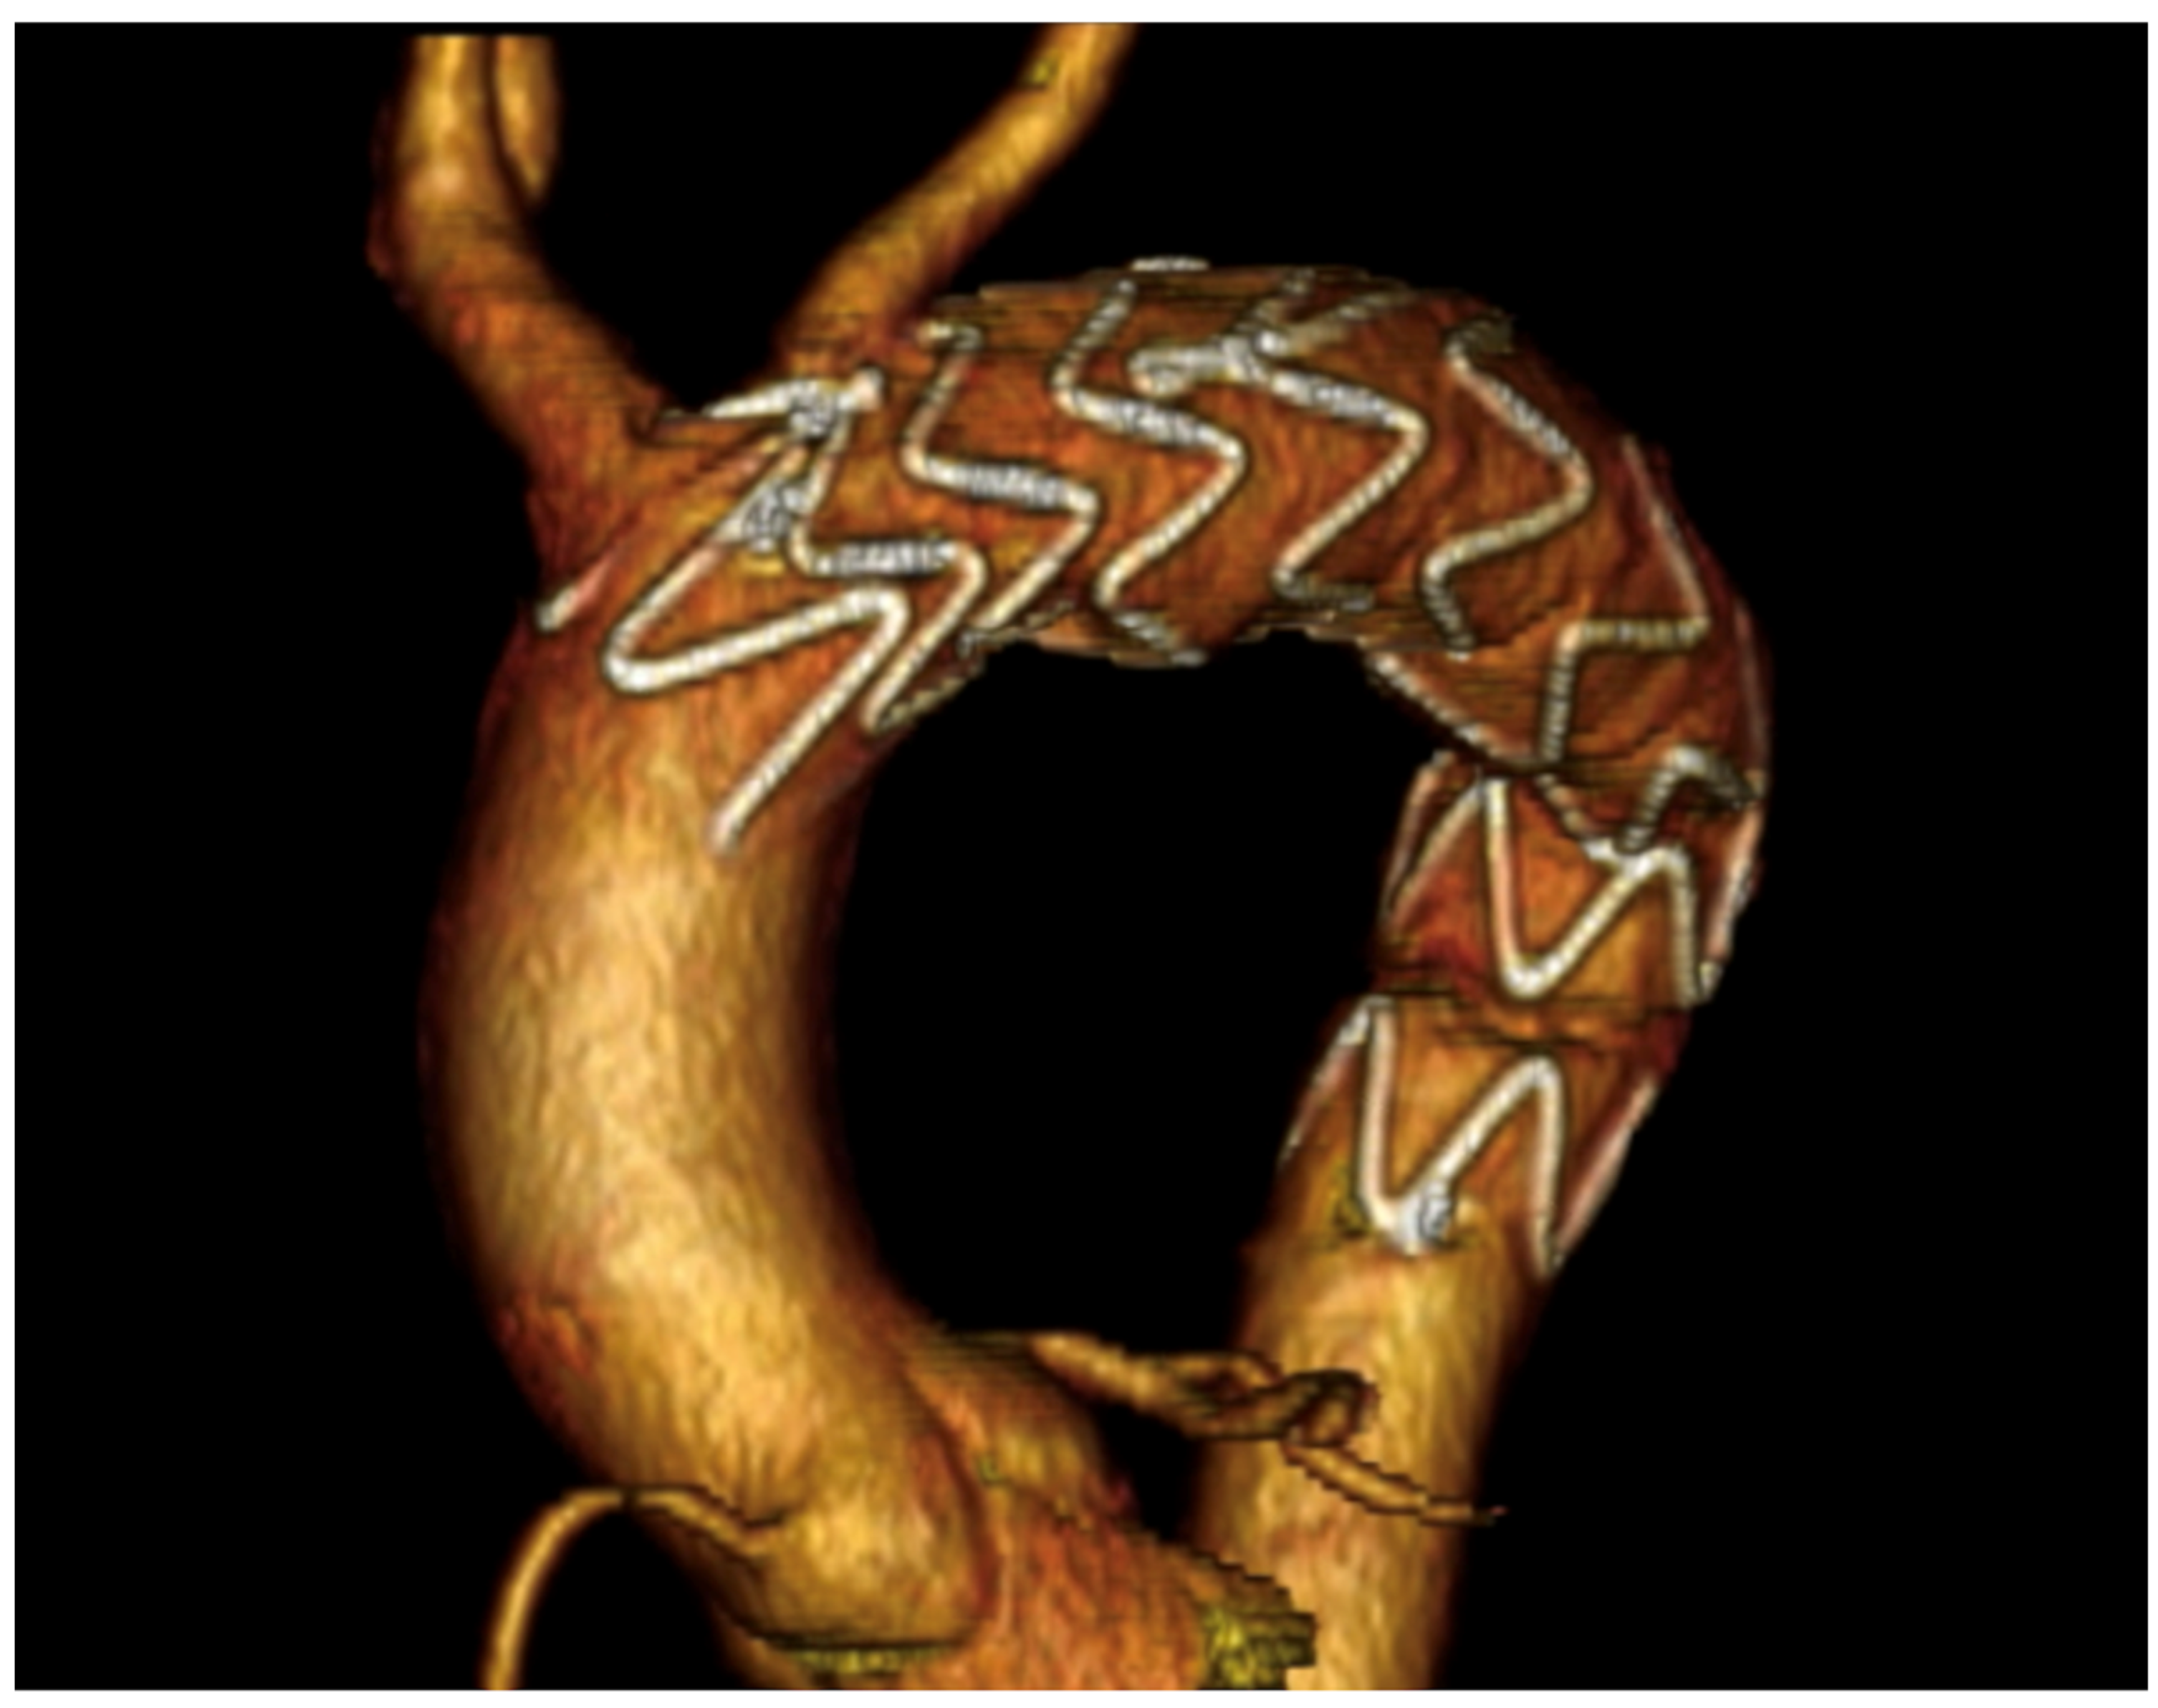

| Current Case-1 | 48 | M | Aortic arch | Cough | 25 years | Hybrid (ET + TEVAR) |